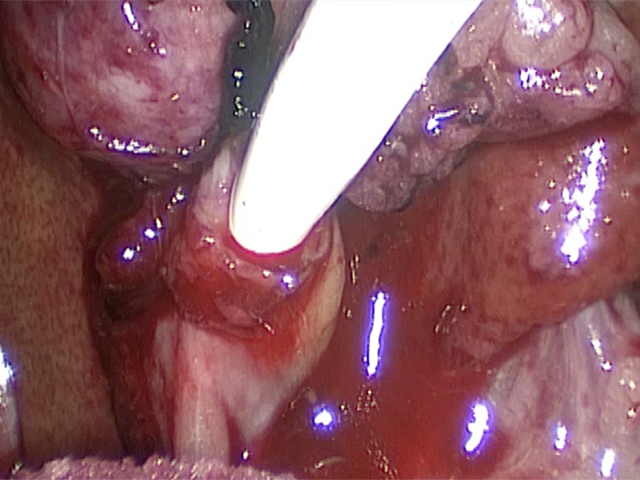

お腹にトロッカーを4本挿入し、そこから鉗子とカメラを入れて胆嚢を肝臓から剥がしていきます。 カメラで拡大しながら見ることができるので開腹手術よりも視野が確保できます。

胆嚢の周囲の脂肪や膵臓、十二指腸が激しく癒着し剥離が困難な状態でした。胆嚢は全く確認することができませんでした。

少しずつ癒着を剥がして胆嚢が確認できるようになってきました。 こんなに癒着していることはあまりないので過去に膵炎や胆嚢炎を起こし苦しい時期があったことが推測されました。 それにしてもなかなか胆嚢はでてきませんでした。

癒着(矢印)がひどく胆嚢を確認することができませんでした。 このように癒着しているときはギリギリで剥がすとひどく出血をおこすことがあるので無理にはがそうとしないで、脂肪の血管に注意しながら脂肪ごと剥がしていきます。

胆嚢の頸部に糸を通し動脈を確保しています。

胆嚢を少しずつ丁寧に肝臓から剥がしています。